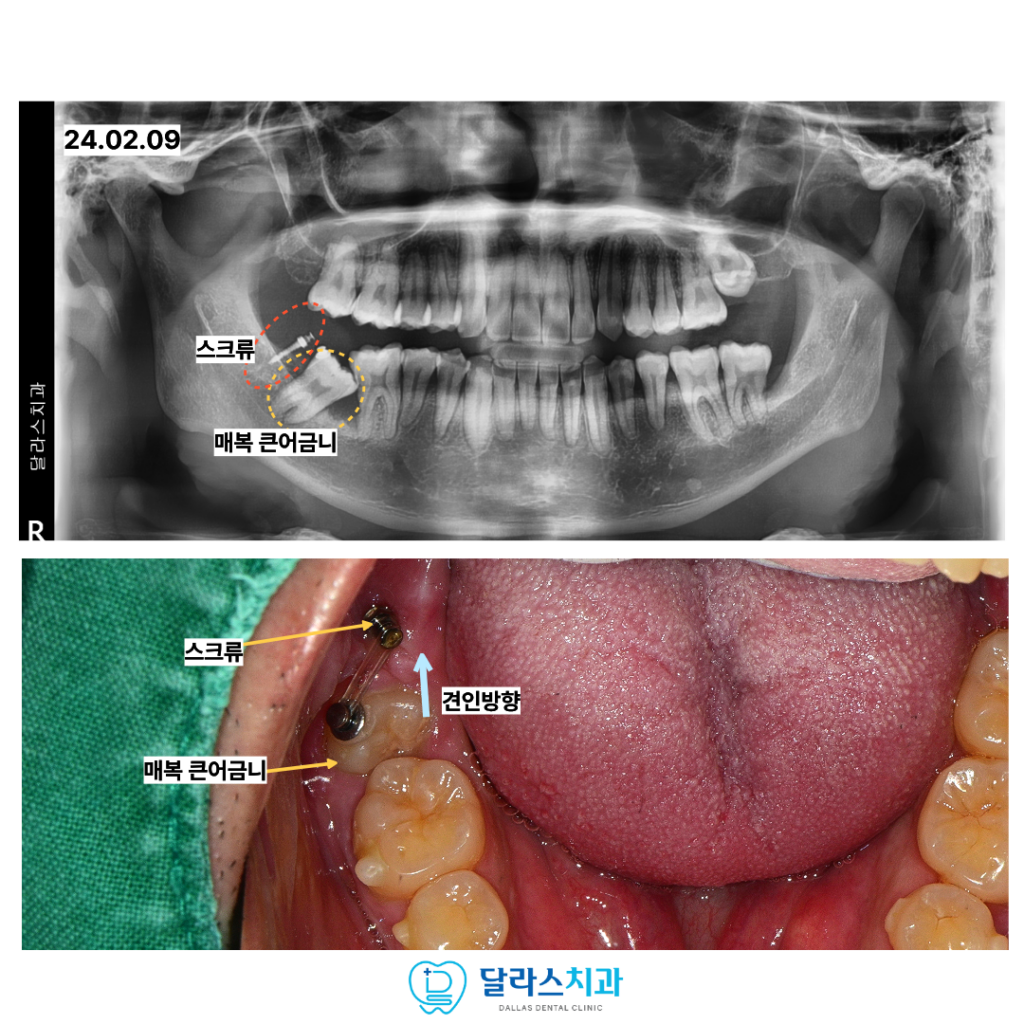

먼저 위쪽의 사랑니를 발치한 뒤 큰어금니를 끌어올릴 수 있도록 스크류를 식립하였습니다.

치료가 진행됨에 매복되어 있던 사십 칠 번 치아가 성공적으로 끌어올려진 모습을 볼 수 있습니다.

이 과정에서 앞쪽 큰어금니의 뿌리 뒷부분이 약간 흡수된 양상이 관찰되었습니다.

이는 매복치가 주변 치아에 미치는 나쁜 영향력을 보여주는 증거이기도 합니다.

만약 이 환자분께서 적절한 시기에 치료를 받지 않고 방치하셨다면

매복된 큰어금니를 잃게 되는 것은 물론이고 인접한 앞쪽의 멀쩡한 큰어금니까지

뿌리 흡수가 심해져 결국 두 치아 모두를 발치해야 하는 최악의 상황에 직면했을 것입니다.

다행히 정확한 진단과 교정적 개입을 통해 소중한 자연 치아를 보존할 수 있었습니다.